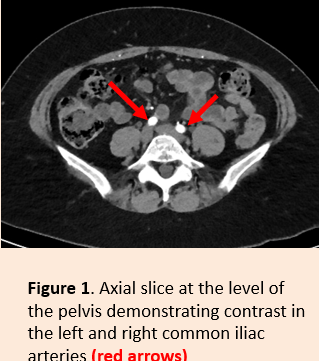

what does the early arterial phase in the pelvis look like

knowt flashcard image

what is the early arterial phase

•The early arterial phase is a contrast-enhanced CT series in which the contrast is still in the arteries and has not reached the organs and other soft tissues.

•The early arterial phase offers optimal vessel demarcation and allows the detection of vascular pathology (e.g. aortic dissection, aneurysms, tumours of blood vessels)